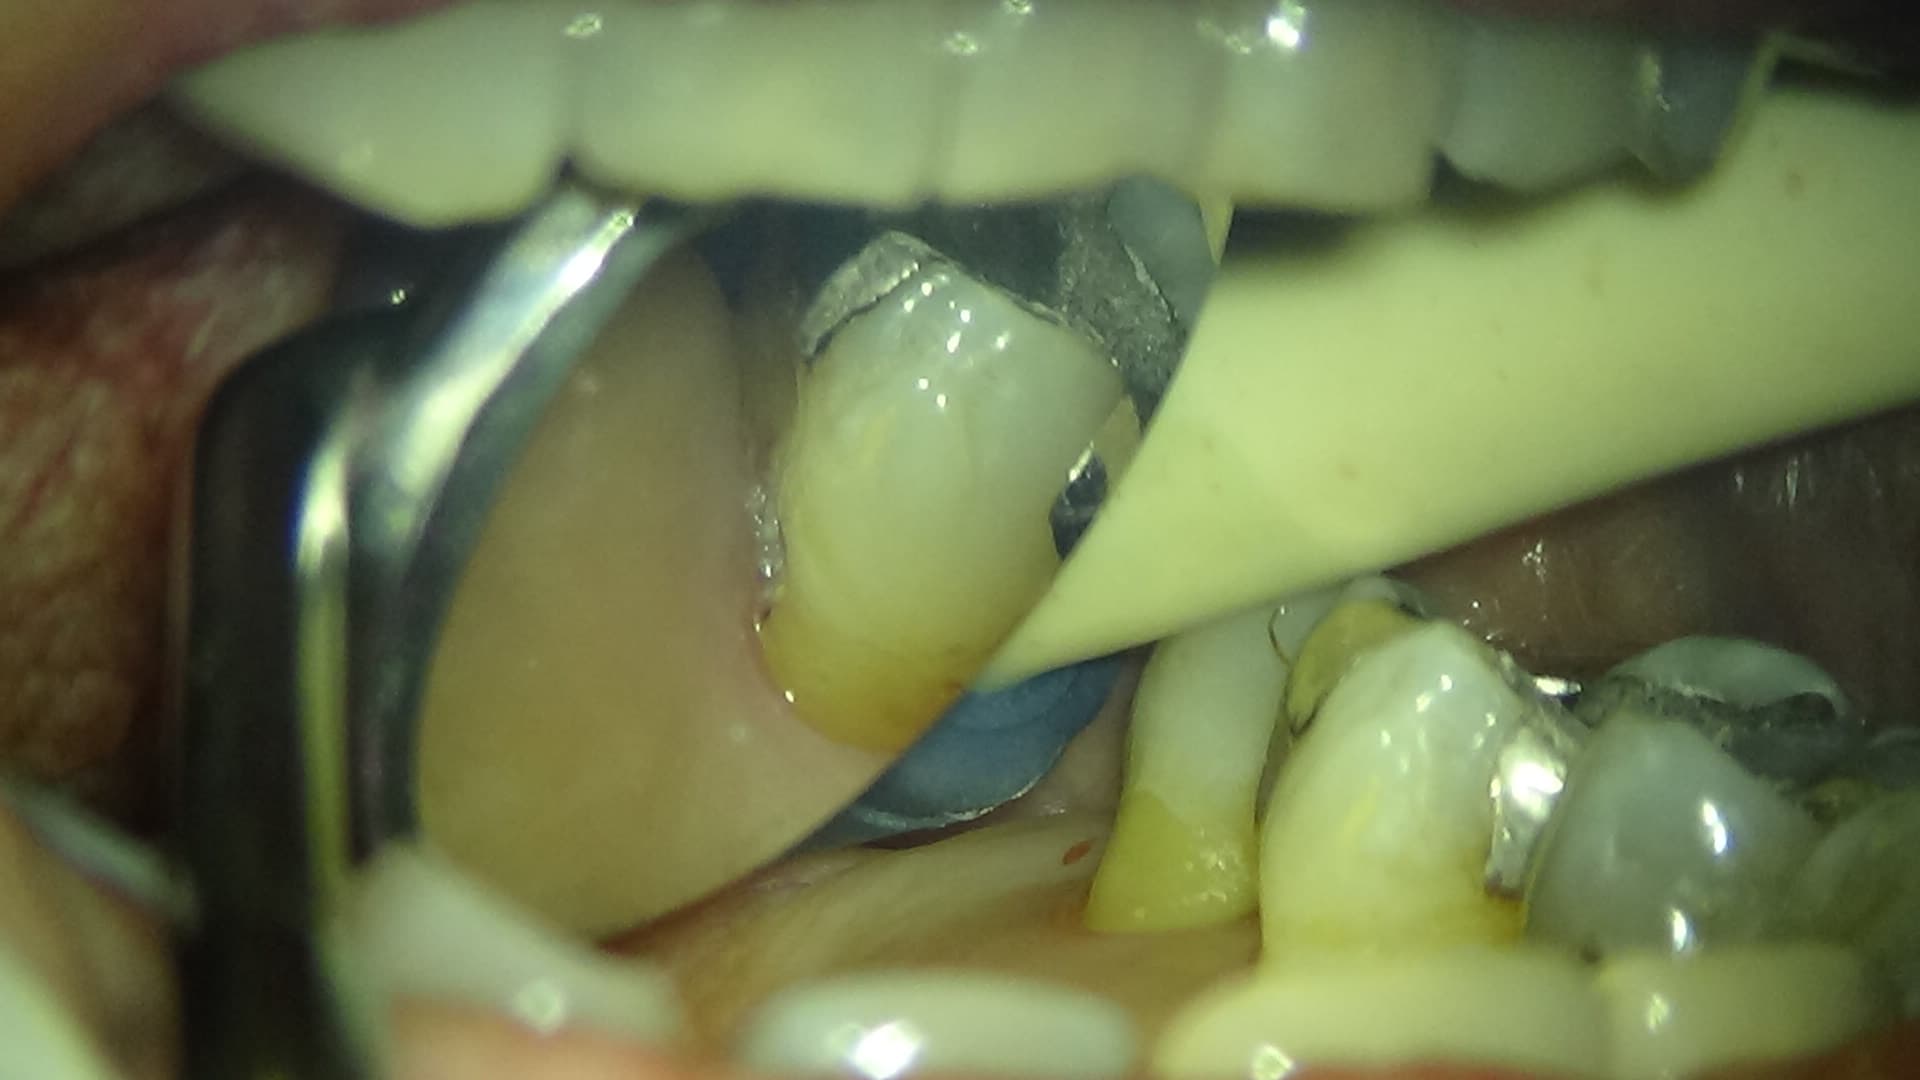

以前、歯周病専門治療で歯周ポケット内の感染源除去をしていた時のことです。

よく見ると、歯の裏側に虫歯が隠れているのがわかります。

初診時にも、虫歯があることはお知らせしていますが、目で見えないところにある虫歯は、痛みも無ければ、なかなかご自身で治療の必要性を感じるのは難しいものです。

滅多に見る事のない映像でもあるので、びっくりされる方もいらっしゃるかもしれませんが、自分の口の中がどうなっているかを知る、良いきっかけにして頂ければと思います。

マイクロスコープの使用は、病気の早期発見・早期治療、そして再発予防の為には欠かせないツールだと感じています。